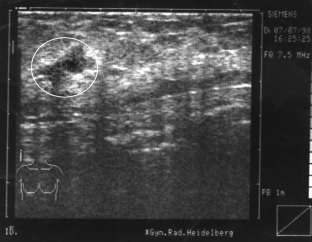

Am Montag kam eine Freundin zu mir, sagen wir, sie heißt Marga (40 Jahre), und war ziemlich aufgelöst. Sie sagte, sie habe einen großen und schmerzhaften Knoten in der linken Brust. Sie war vor ein paar Tagen deshalb bei einer Untersuchung und der Prof. sagte, sie müsse ihn dringend, und zwar so schnell wie möglich, rausnehmen lassen, denn die Gefahr sei groß, daß er streut. Sie selbst hat auch das Gefühl, daß der Knoten bösartig ist. Sie hat das Ultraschallbild und zeigt es mir. Man sieht einen fast runden großen, dunklen Fleck mit vier grauen unscharfen Ausbuchtungen. Marga nennt sie „die vier Ecken“.

Vorher: